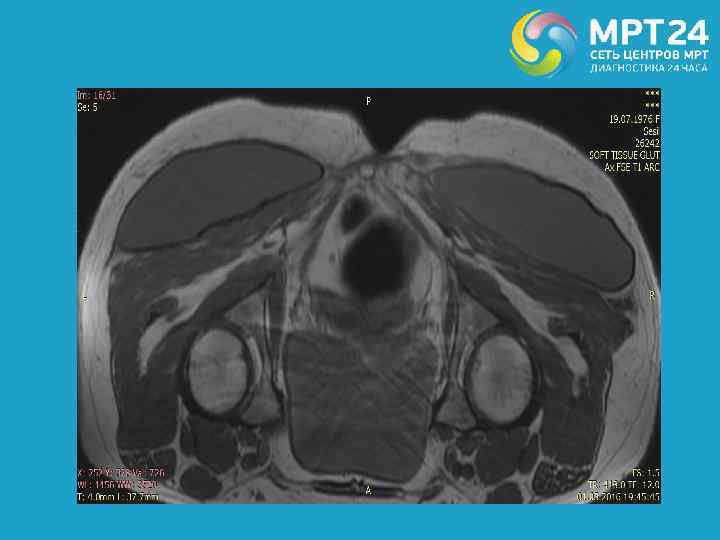

Собственное наблюдение. Женщина 40 лет, состояние после глютеопластики, без признаков нарушения целостности имплантов.